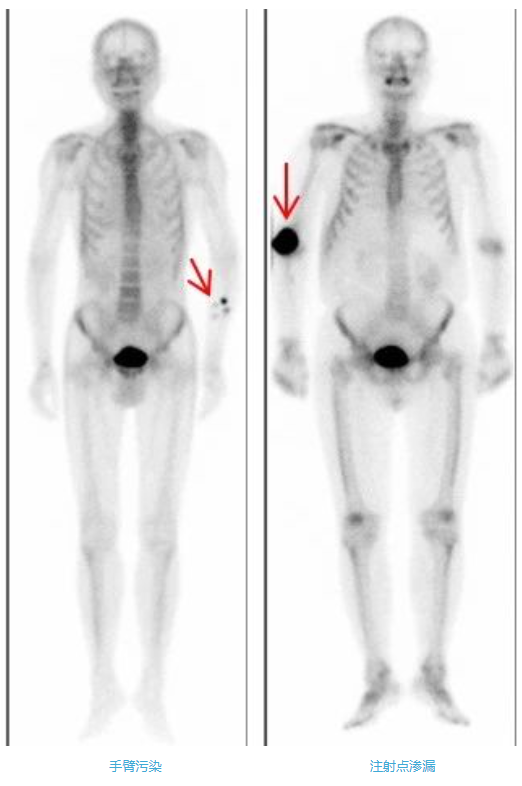

3、正確按壓注射點(diǎn)

當(dāng)您一側(cè)上肢骨有癥狀時(shí),要提醒護(hù)士在對(duì)側(cè)的血管注射。拔針后,需要您對(duì)針眼處稍用力按壓約5-10分鐘,按住不要揉,否則會(huì)造成注射部位異常放射性濃聚影,影響圖像質(zhì)量。如果按壓的手指被血液或注射液污染,要及時(shí)沖洗,不要污染衣物或皮膚。